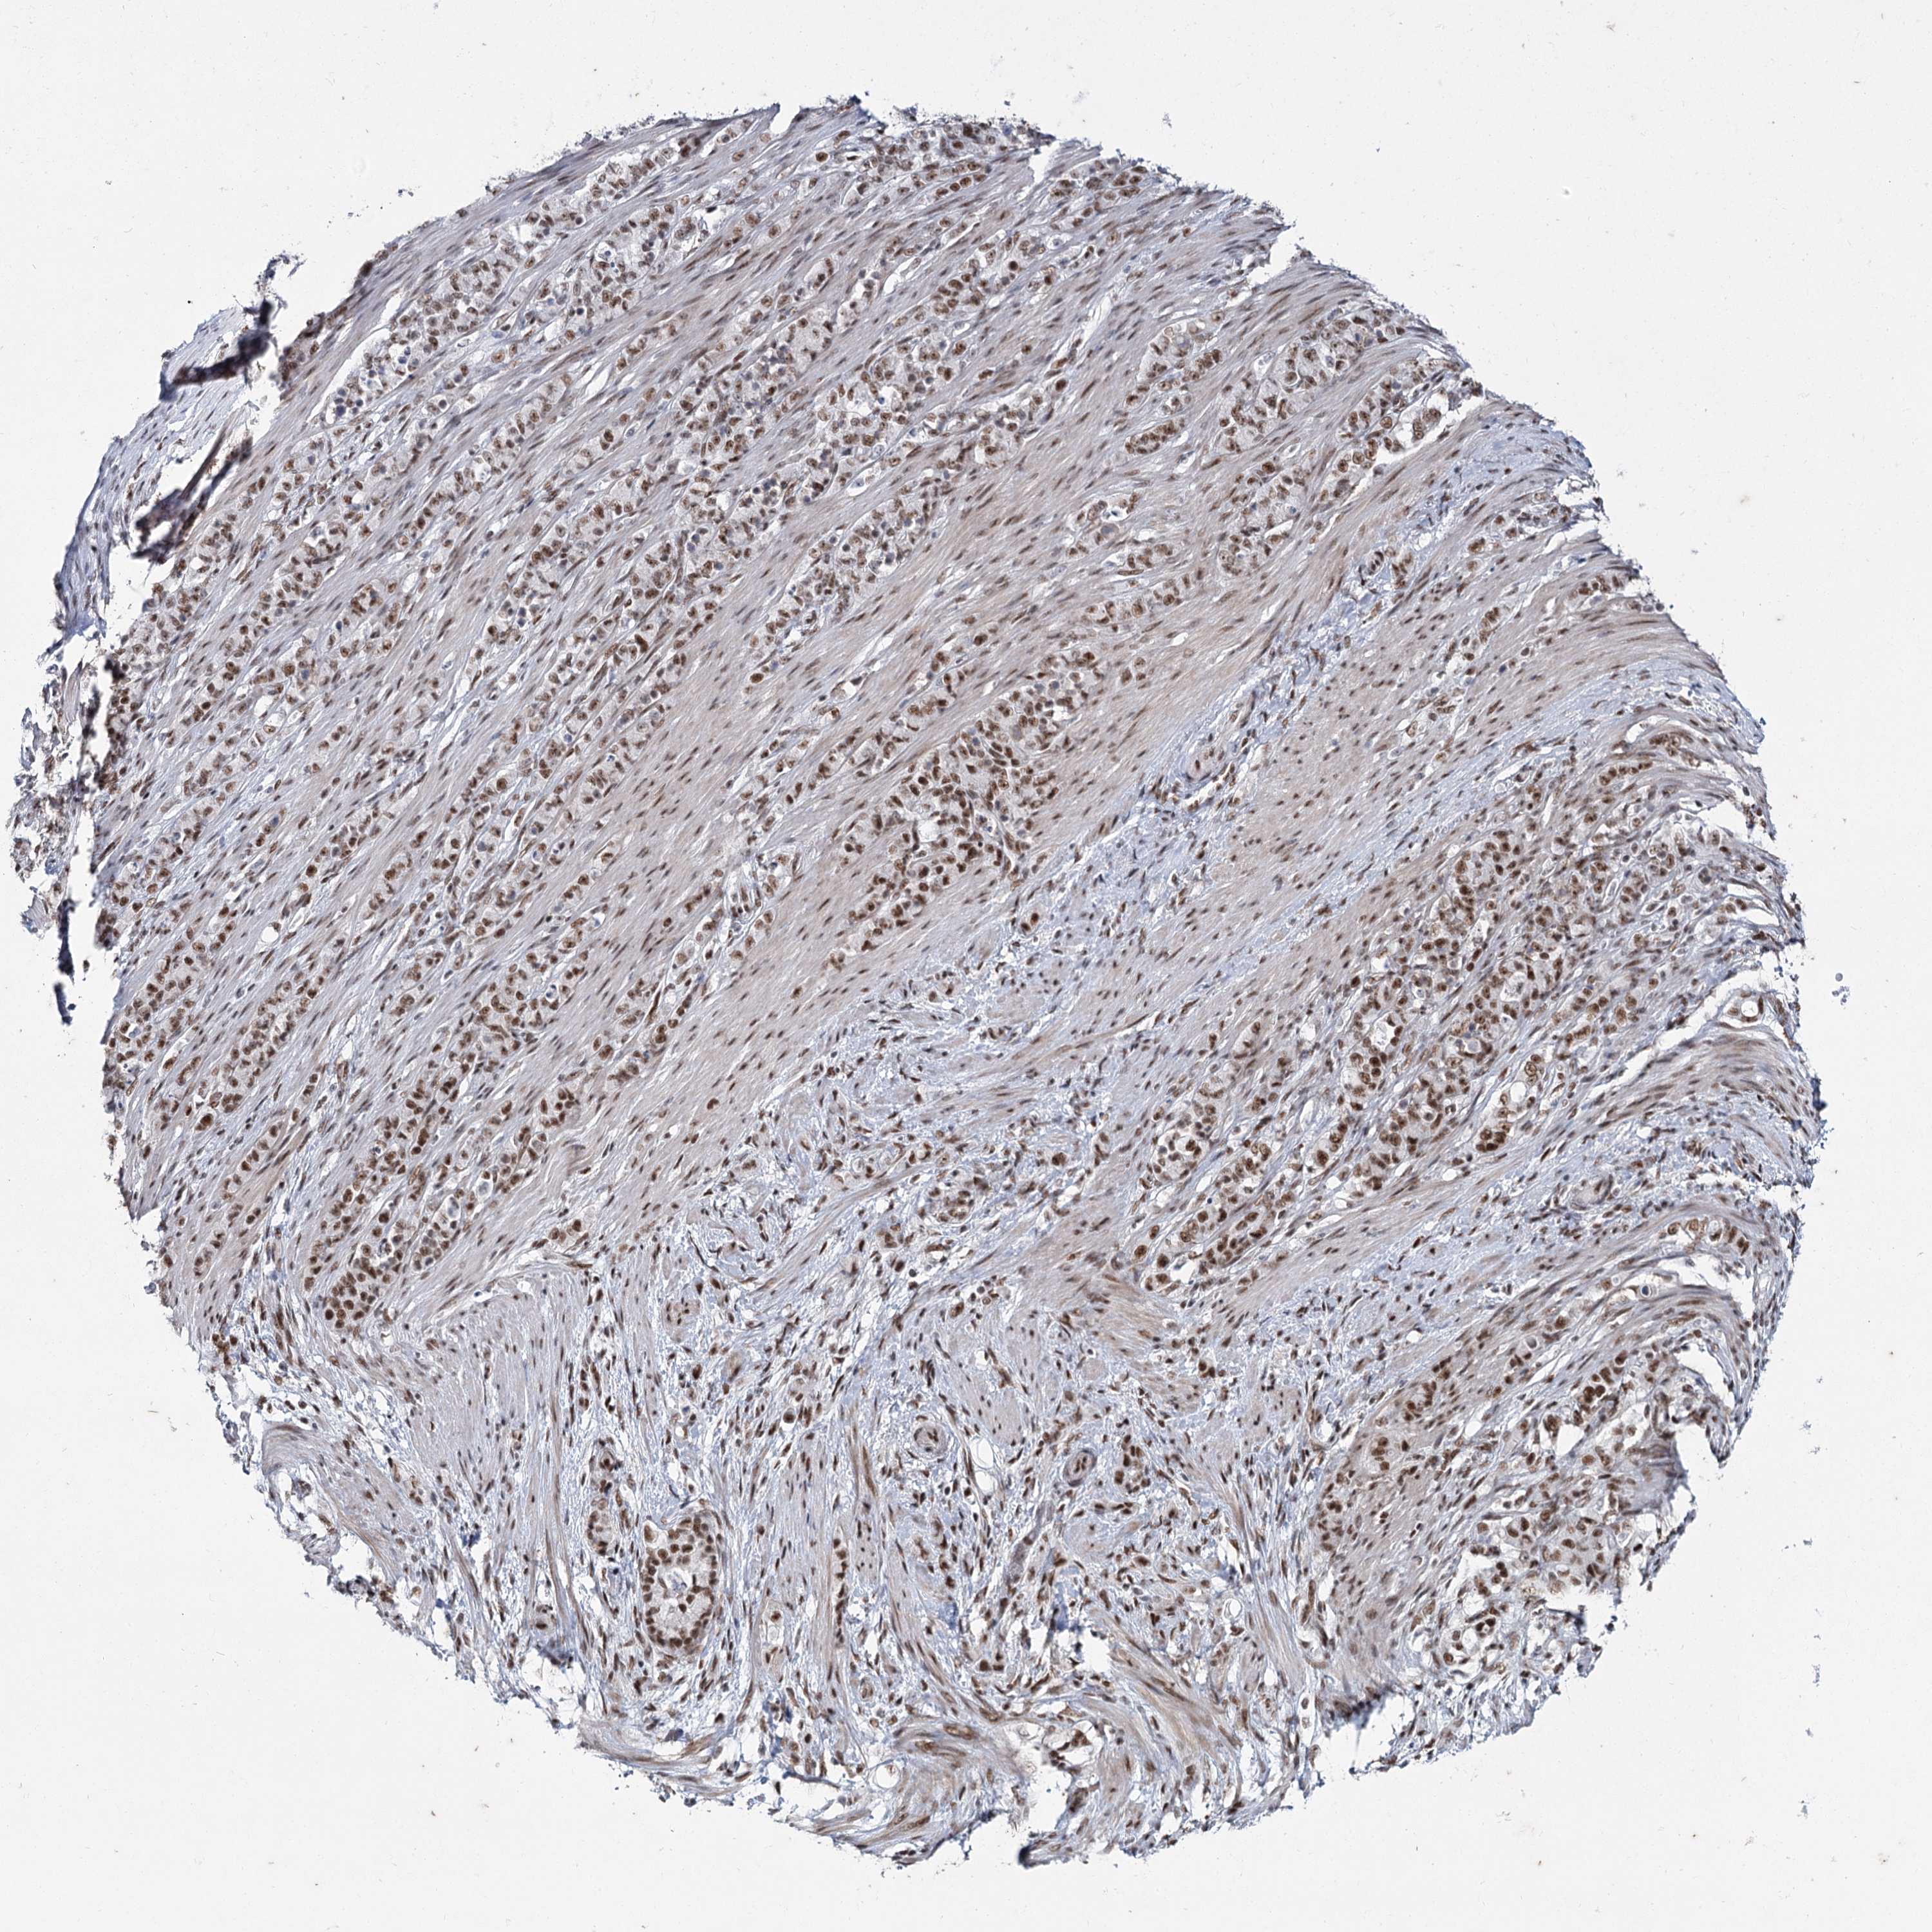

STOMACH CANCER - Protein expressioni

A mouse-over function shows sample information and annotation data. Click on an image to view it in a full screen mode. Samples can be filtered based on level of antibody staining by selecting one or several of the following categories: high, medium, low and not detected. The assay and annotation is described here.

Note that samples used for immunohistochemistry by the Human Protein Atlas do not correspond to samples in the TCGA dataset.

Antibody stainingi

Antibody staining in the annotated cell types in the current human tissue is reported as not detected, low, medium, or high, based on conventional immunohistochemistry profiling in selected tissues. This score is based on the combination of the staining intensity and fraction of stained cells.

Each image is clickable and will lead to virtual microscopy that enables deeper exploration of all samples and also displays staining intensity scores, fraction scores and subcellular localization as well as patient and tissue information for each sample.

Antibody HPA035601

Antibody HPA035602

Staining

High

Medium

Low

Not detected

Intensity

Strong

Moderate

Weak

Negative

Quantity

>75%

75%-25%

<25%

None

Location

Nuclear

Cytoplasmic/membranous

Cytoplasmic/membranous,nuclear

Adenocarcinoma, NOS